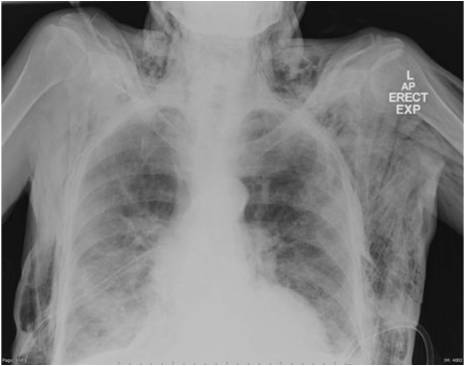

weekly clinical round for undergraduate from 8 to 11 AM during which interpretation of CHEST X rays was done for all cases of cardiothoracic surgery, gived by 2 staf member for 3 months